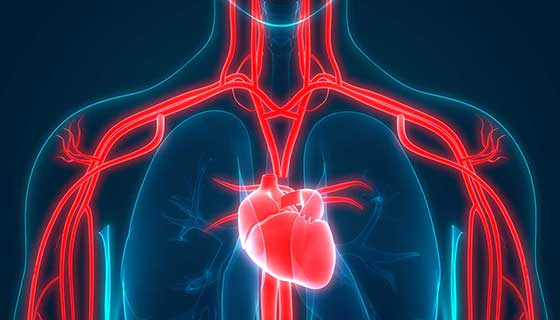

Arteries are blood vessels that transport blood from the heart to other parts of the body. Over time, they can accumulate plaque deposits, which can hinder blood flow and increase the risk of heart disease. To prevent these issues, there are a variety of recipes and foods that can help cleanse the arteries and maintain heart health. Below, we will explore some of these: